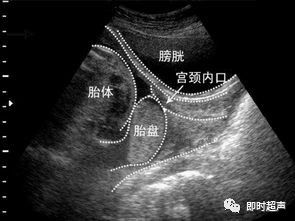

前置胎盘的定义:正常的胎盘附着于子宫体部的前壁、后壁或侧壁,远离宫颈内口。妊娠28周后,胎盘仍附着于子宫下段,其下缘达到或覆盖宫颈内口,位置低于胎儿先露部,则称为前置胎盘。而在28周前称为胎盘前置状态,妊娠中期胎盘前置状态常因胎盘“移行”而发生变化,也就说妊娠中期的胎盘可能会随孕周增加而上移,从而“远离”宫颈内口。因此准妈妈们如果在妊娠中期发现胎盘前置状态也不必过于紧张,需要的是定期复查腹部或者阴道超声。

前置胎盘的分类:根据胎盘下缘与宫颈内口的关系,将前置胎盘分为3类:

1.完全性前置胎盘(中央性前置胎盘):胎盘组织完全覆盖宫颈内口。

2.部分性前置胎盘:胎盘组织部分覆盖宫颈内口。

3.边缘性前置胎盘:胎盘下缘附着于子宫下段,下缘达到宫颈内口,但未超越宫颈内口。

另外,在胎盘下缘未覆盖宫颈内口,但是距离宫颈内口比较近,我们称为低置胎盘:胎盘附着于子宫下段,边缘距宫颈内口的距离<20 mm,此距离对临床分娩方式的选择有指导意义。由于低置胎盘可导致临床上的胎位异常、产前产后出血,对母儿造成危害,临床上应予重视。